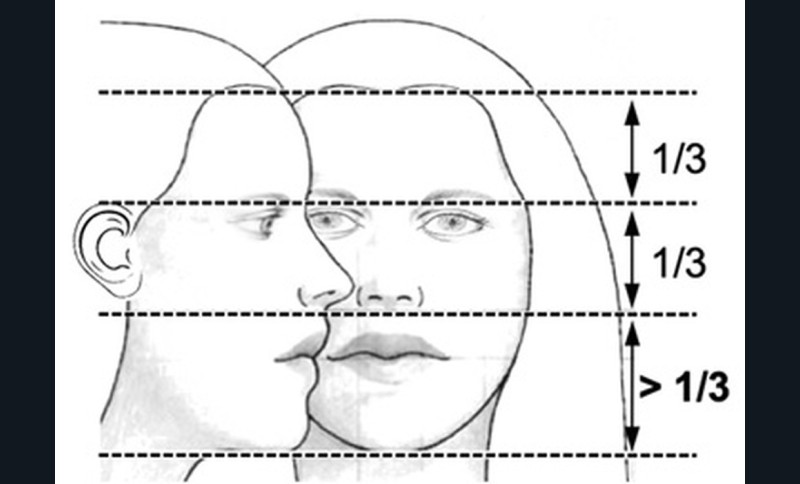

L’examen clinique orthodontique débute par un examen exobuccal de face et de profil qui permet à l’orthodontiste d’identifier certains signes d’appel du Sahos [4]. L’examen de face apprécie la forme globale du visage, la typologie et la symétrie faciale (fig. 5). Des signes caractéristiques sont souvent rapportés chez les enfants suspectés de Sahos : incompétence labiale au repos, hypotonie de la lèvre supérieure avec un angle naso-labial augmenté, visage allongé, orifices narinaires étroits et pincés et présence de cernes (fig. 6a) [5]. Ce sont des indicateurs indirects d’une obstruction ou d’un rétrécissement nasal et d’une ventilation buccale [5-6].

L’examen de profil apprécie les rapports maxillo-mandibulaires et la convexité du visage dans le sens antéropostérieur. Chez les enfants apnéiques, on note généralement la présence d’un profil convexe rétrusif avec un menton en retrait, associé à des dépôts graisseux si l’enfant est en surpoids. Une hypotonie de la lèvre supérieure, qui se traduit par un angle naso-labial ouvert, signe d’un hypo-développement maxillaire, est souvent présente [7]. Enfin, on observe parfois une contraction du muscle mentonnier associée à une occlusion labiale forcée (fig. 6b).